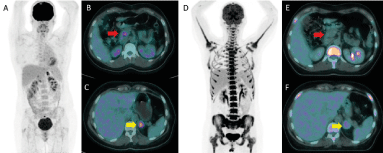

In April 2012 a 46-year-old woman, had a left pneumectomy with R1 resection at the left pulmonary artery for an 11 cm high grade intimal sarcoma. Pathology reported a proliferation of polymorphic spindle cells with pleomorphic, hyperchromatic nuclei, combined with multiple vascular invasion. Immunohistochemical staining results were positive for desmin, α-smooth muscle actin and MDM2, and negative for CD31, CD34, and p63 (Figure 1). This surgery was followed by a new resection one month later in R0. Twenty lymph nodes were resected and found negative. In February 2014, during her follow up Fluorodeoxyglucose positron emission tomography (18F-FDG PET/CT) showed an hypermetabolic adrenal left mass (maximum Standard Uptake value, SUVmax 8.6) and a mass of the head of pancreas (SUVmax 6) with no other hypermetabolic lesion noted, highly suspicious of metastatic relapse (Figure 2). The patient was asymptomatic and laboratory tests of liver and pancreatic biochemical parameters (AST, ALT, ALP, GGT, bilirubin, lipase) were within their respective normal range. Tumor biomarker for adenocarcinoma of hepatobiliary origin CA 19-9 was within normal range as well.

The metastatic nature of adrenal mass was confirmed by biopsy, showing similar pleomorphic spindle cells, with a matching immunohistochemical profile, consistent with an intimal sarcoma origin. In this context, the patient was treated with systematic chemotherapy of doxorubicine/ifosfamide. After 6 cycles, a new 18F-FDG PET/CT revealed a metabolic complete response of pancreatic lesion and a partial metabolic response of adrenal (residual SUVmax 4.7) (Figure 2). The Magnetic Resonance Imaging (MRI) confirmed the complete response of the intrapancreatic lesion. After multidisciplinary discussion we decided to proceed to left adrenal resection. The pathology showed a 4.5 cm metastases. Six months later, the follow up imaging revealed a new lesion at the right adrenal compatible with metastases. A contralateral adrenalectomy was agreed and confirmed the metastases. Since replacement therapy by glucocorticoid started.

Figure 2. 18F-FDG PET/CT before (A-B-C) and after (D-E-F) chemotherapy. Complete metabolic response of the pancreatic lesion (red arrow) and partial metabolic response of the left adrenal lesion (yellow arrow)